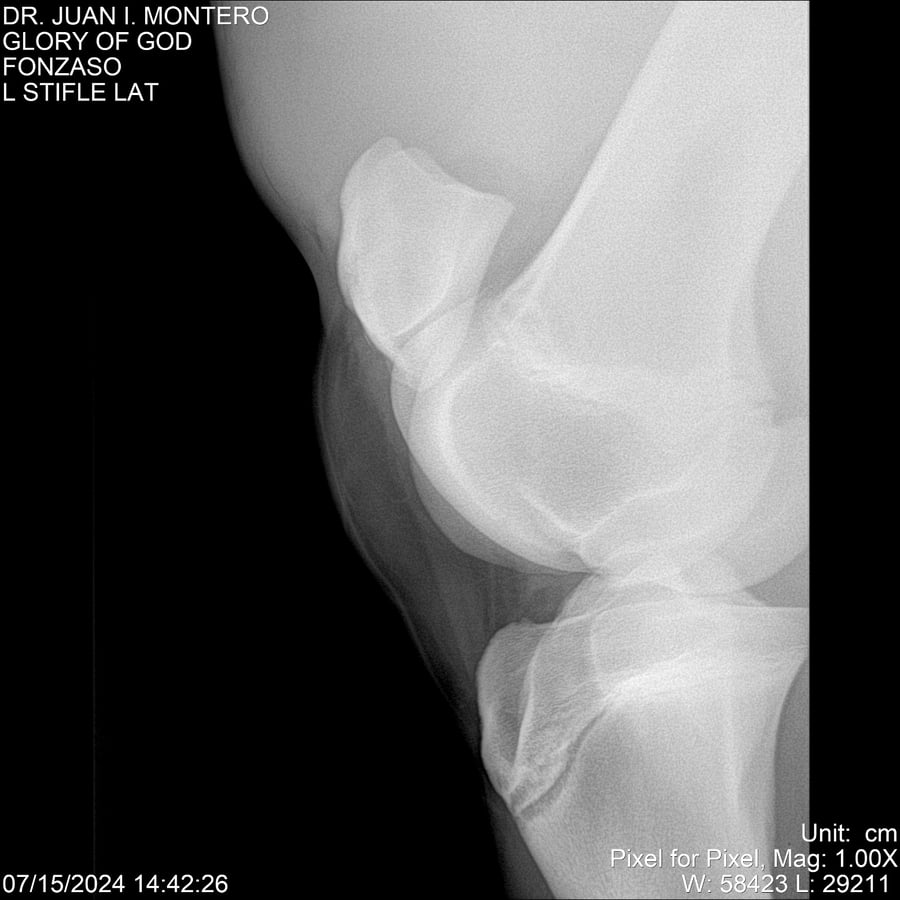

LOTE 10, GLORY OF GOD 🔥 🔥 🔥 Lote Anterior Volver al remate Lote Siguiente Ficha Contacto Montevideo - Ficha del Lote Identificador: #281389 Categoría: Yeguarizos Montevideo - 115 Visualizaciones ClicData Contacto Empresa: Abelenda N. R., Walter Hugo Nombre*: Teléfono* : E-mail* : Mensaje Enviar Registrese gratis Este contenido Exclusivo está disponible sólo para usuarios registrados Ingresar